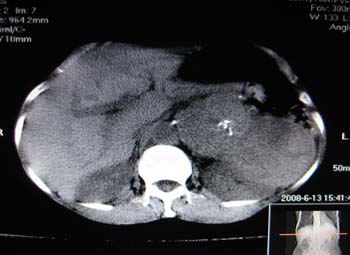

女,65岁,左上腹痛。

肝脏占位  脾脏及胰腺病变   请提供病史

肝脾胃左肾胰都显示不正常啊

病史不详,肝、脾、胰都有占位,谁是原发?

淋巴瘤及肝癌(转移瘤?)可不可以不用一元论解释呢。

胰腺癌伴脾脏侵犯并肝内转移可能性大  建议增强扫描  否则没有确凿的依据

考虑姨尾癌,腹膜后转移\\肝转移

没有病史,没有强化,那就只有猜了,我看病灶很像肝、脾及腹腔多发脓肿,这只是我的意见,

图像欠清,病灶与胃脾胰肾上腺关系显示欠清,建议增强,肝脏考虑转移瘤.

多脏器占位,腹膜后淋巴结增大,淋巴瘤?建议增强扫描